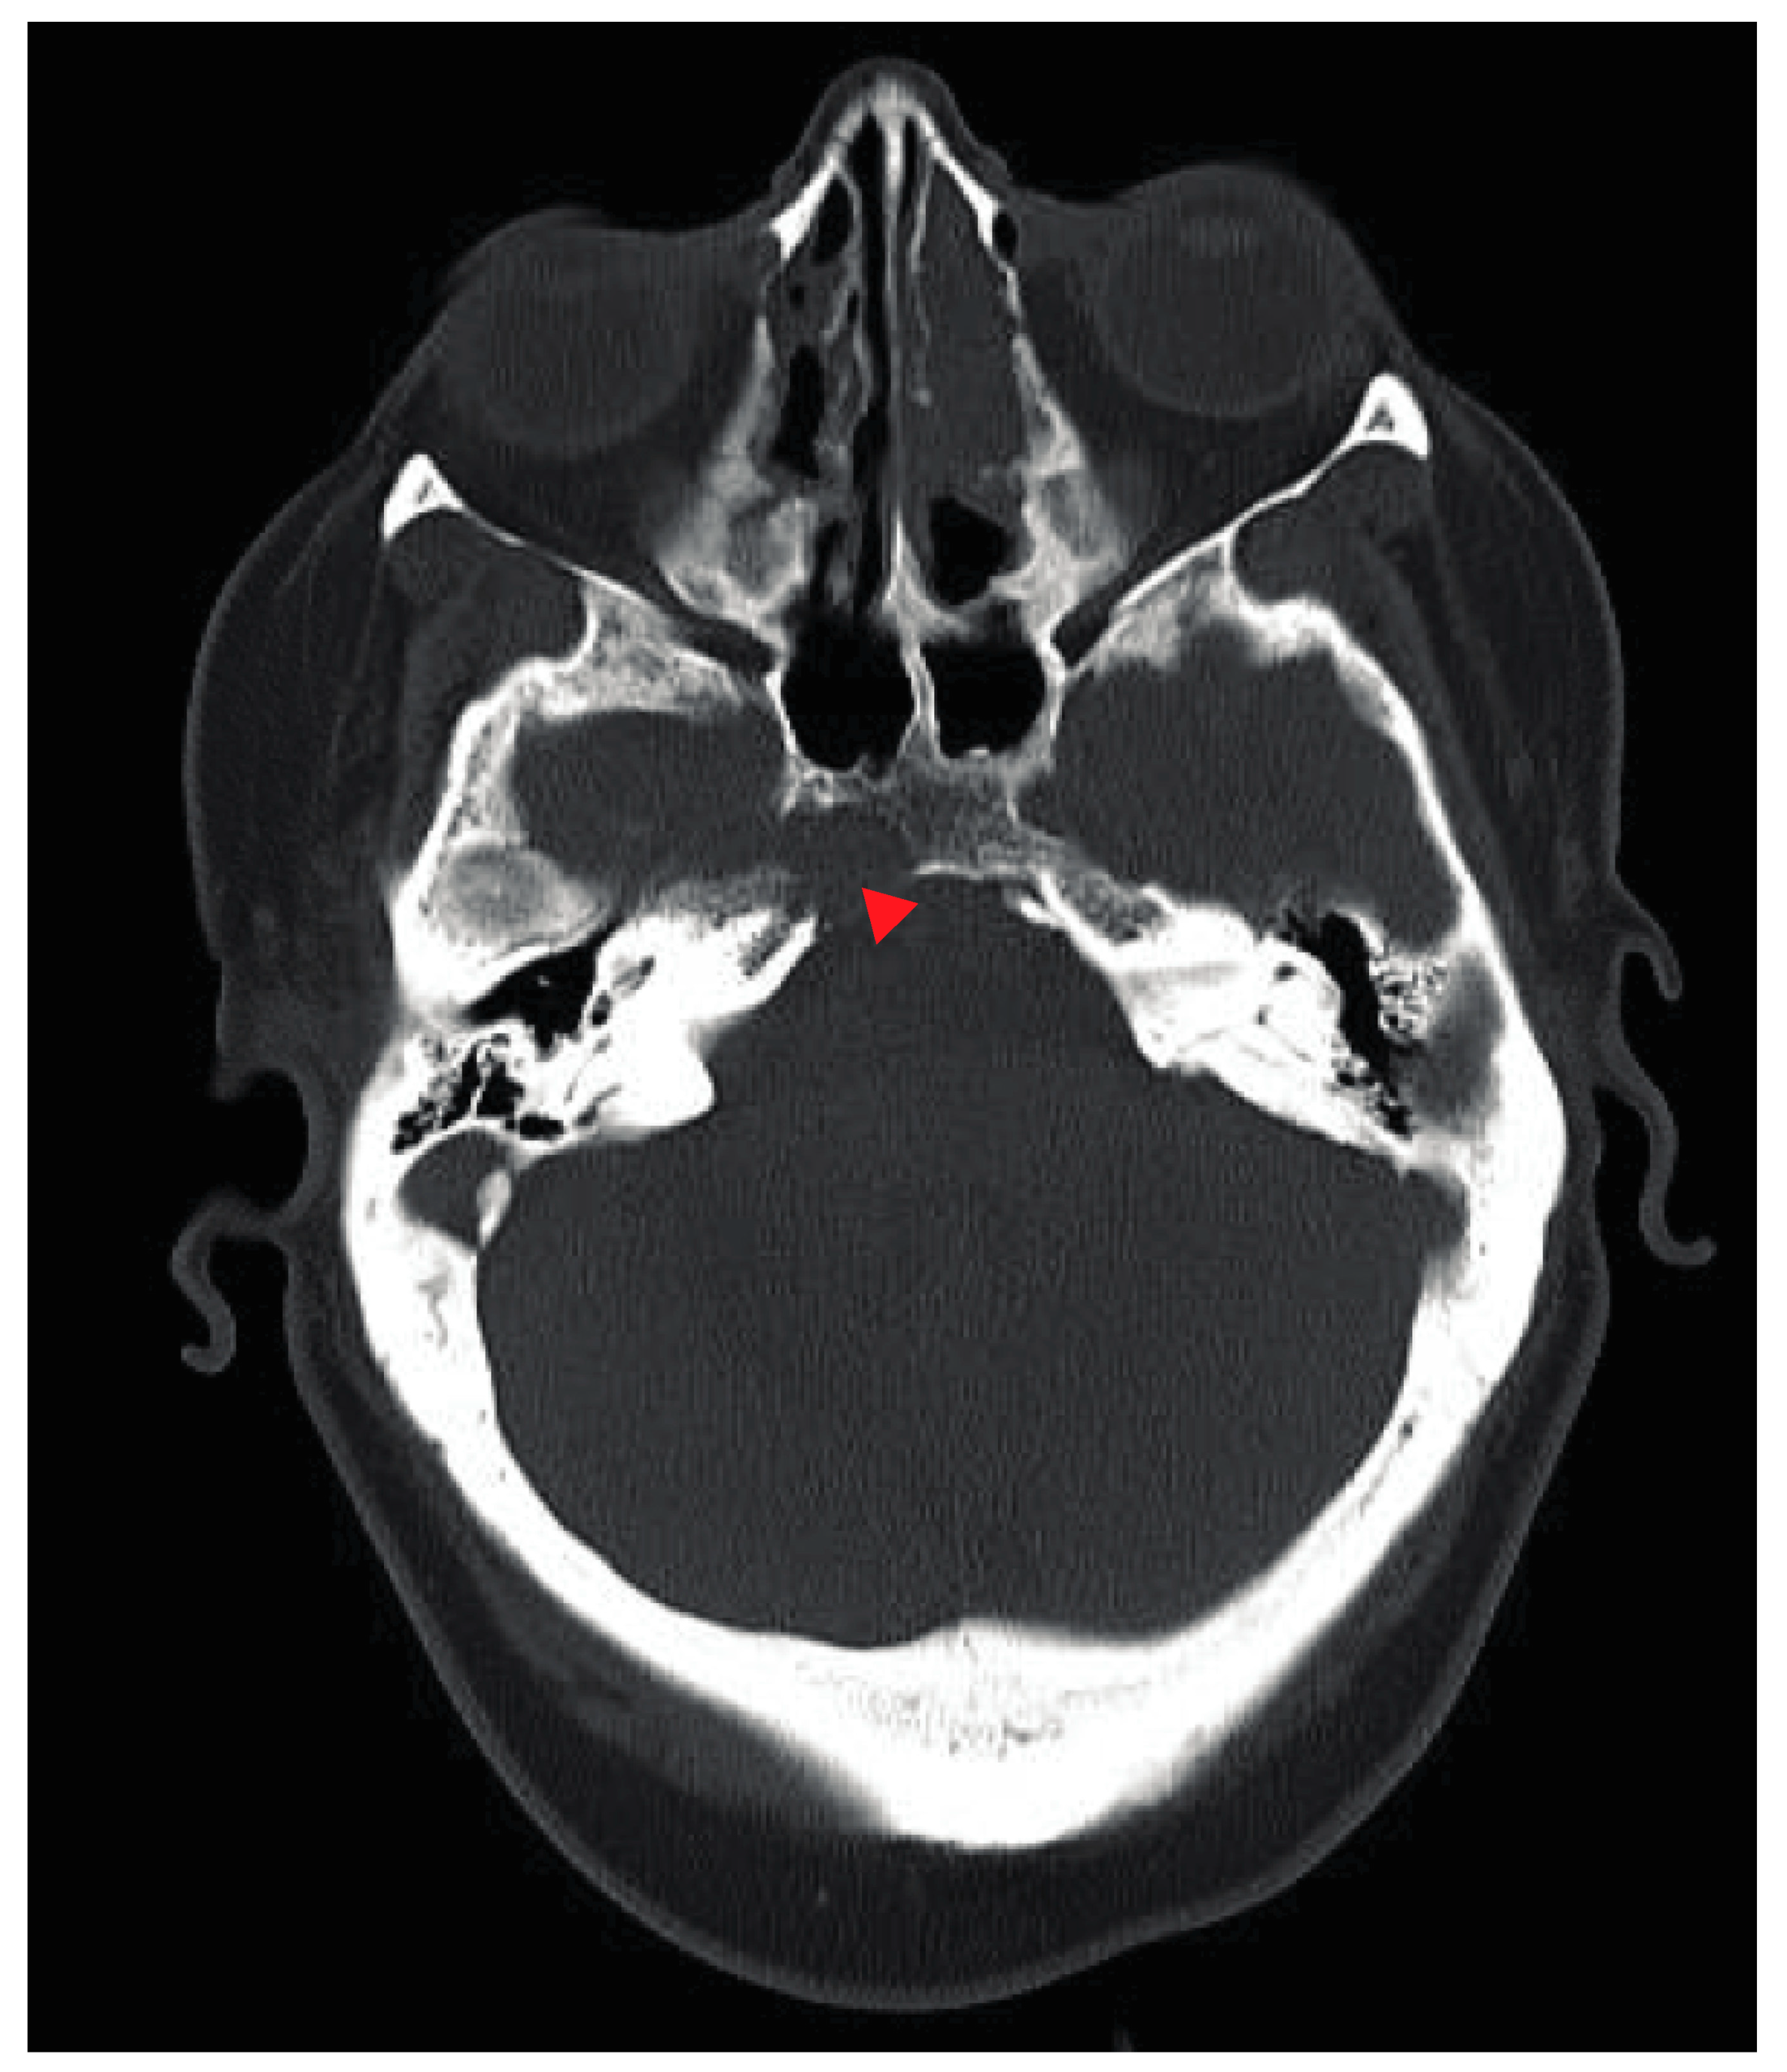

Abducens Nerve Palsy as Initial Presentation of Multiple Myeloma and Intracranial Plasmacytoma

2. Case Presentation